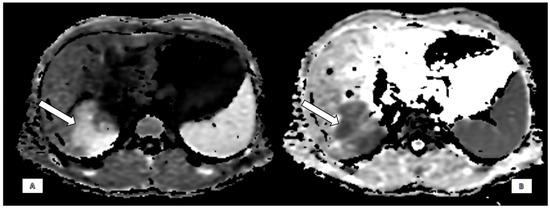

2.2. Imaging